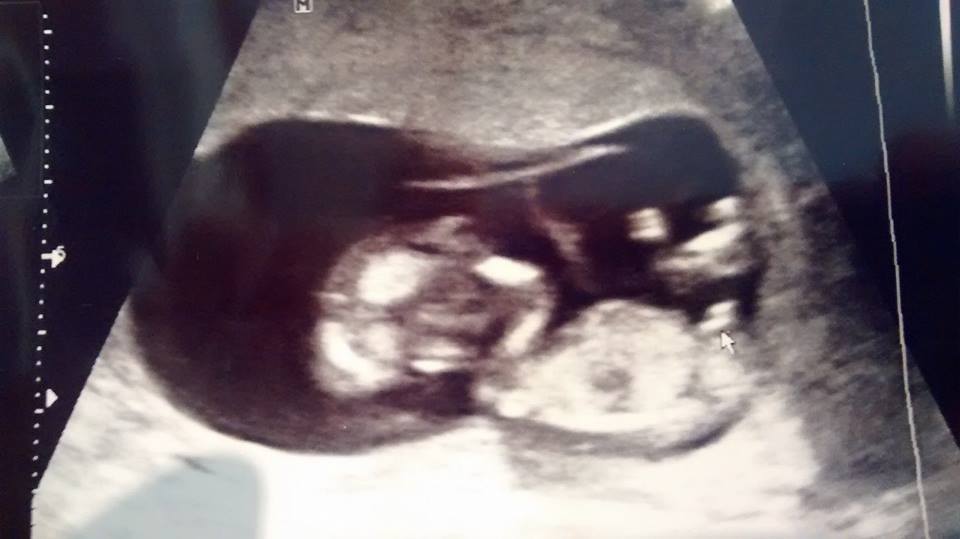

Had my 12 week US yesterday and the tech was pretty positive on her guess. I'm wondering what you ladies think. Thanks in advance!